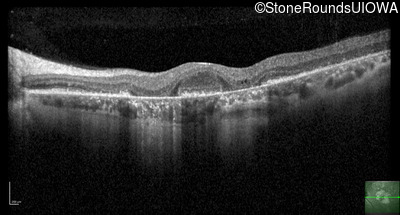

Optical Coherence Tomography - Left - 20/20 -2

Exemplar / OCT Stack